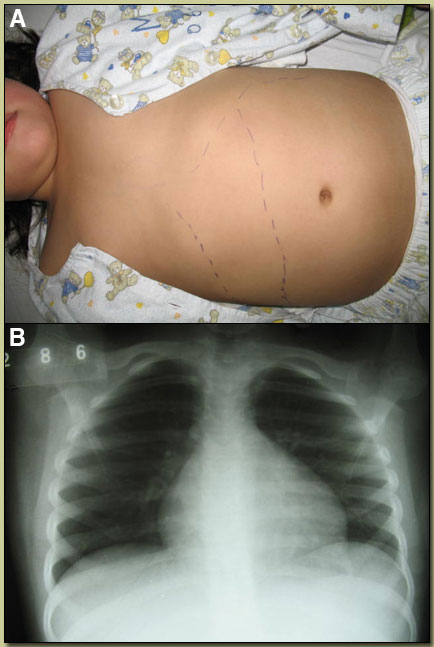

| Diagnosis: Acute Chagas’ Disease due to Trypanosoma cruzi. |

T. cruzi is a single-celled protozoan found in two forms in infected humans. The infective trypomastigotes are found in the acute phase of disease circulating in the bloodstream. After they infect muscle, nerve and other cells, they transform into small 3 micron intracellular amastigotes as the infection enters the chronic phase. Amastigotes replicate slowly by binary fission and are released after host cell rupture to infect other host cells. Initial human infection occurs when the vector, large triatomine bugs (5-45 mm in length), take a blood meal at the end of which they defecate on the victim. The victim then self-inoculates with trypomastigotes present in the feces by rubbing on the irritated spot and the parasites enter by any small break in skin integrity or often through intact mucosal tissues such as the conjunctivae. In the acute stage of infection, such as in our case, the clinical manifestations can vary widely. Most infections are asymptomatic, up to 20% have a mild undifferentiated febrile syndrome, and less than 5% have a severe or fatal illness that is usually associated with myocarditis, heart failure or meningoencephalitis. The incubation period is 1-2 weeks, hepatosplenomegaly is common and acute disease lasts 1-3 months. An inoculation chancre or chagoma is seen in about half of cases and when the entry is via the conjunctiva, unilateral bipalpebral orbital edema (Romana’s sign) is seen. Non-specific EKG changes are common, with evidence of myocarditis is more severe cases. The severe conduction abnormalities seen in chronic disease are uncommon in acute disease. Patients in the chronic phase of disease, have progressive infection of myocardial and automonic nervous tissue and present with cardiomyopathy, cardiac conduction abnormalities, and gastrointestinal disease including megaesophagus and mega-colon. The alarmingly poor survival curves in individuals who manifest clinical cardiac cardiac disease have now been clearly elucidated [see article published this week in NEJM]. Unlike the acute phase where parasites are present in circulating blood, diagnosis of chronic cases can be difficult and usually depends on serology, or, optimally where available, PCR of blood. Human Chagas’ disease is found in all countries of the Americas from the southern USA to Argentina and Chile. The majority of the 10 million infected individuals are found in Brazil, though Bolivia has the highest seroprevalence rates. There are more than a hundred species of triatomine bugs in the Americas but most human disease is due to Triatoma infestans, Rhodnius prolixus, and Panstrongylus species. The vectors generally live in thatched roofs and cracks in the walls of poorly constructed homes in impoverished rural areas. More than 100 mammal species can act as reservoirs including dogs, cats and guinea pigs. In Peru, limited foci of Chagas’ disease have been described with highest risk in Southern Peru near Arequipa. Posuzo, where this child lives, is not a previously known endemic area. Extensive search of her house by an entomology team failed to find any triatomine vectors, but several uninfected Panstrongylus geniculatus [Image D] were found in palm trees adjacent to the house and are the presumed local vector. While the benefit of treating chronic cases is controversial with existing drugs, consensus is that specific treatment is beneficial in acute cases. Nevertheless complete parasitologic cure likely occurs in only about 50% of acute cases. The patient was begun on a 60-day course of benznidazole, which she is tolerating well. One month after initiation of therapy she is markedly improved but still with some low grade fever. Repeat echocardiography shows cardiac function and size within normal limits.